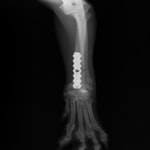

Locking Compression Plate

LCPは、スクリュー(ネジ)とプレート(金属の板)をロックする特殊な構造により骨折部位を固定する新しい世代のプレートシステムです。ひとつのホールでロッキングスクリューとスタンダードスクリューの使用を選択できるユニークな構造をしているため、骨折断端間の圧迫を目的とした従来型プレート固定法に加え、高い角度安定性を有するロッキングスクリューを用いた固定法の選択が可能です。従来のプレートシステムでは困難だった部分の骨折や癒合不全の症例に高い治療効果をもたらします。

Locking compression plate system の特徴

1.骨膜上の血行障害は最小限

2.高い角度安定性

3.プレート設置時の整復位喪失の防止

4.スクリューのルースニング(ゆるみ)の防止

5.コンビネーションホール

6.粗鬆骨における固定性の向上

7.1.5mmと薄いプレートのため、超小型犬にも使用しやすい

8.抜去が不要となることが多い